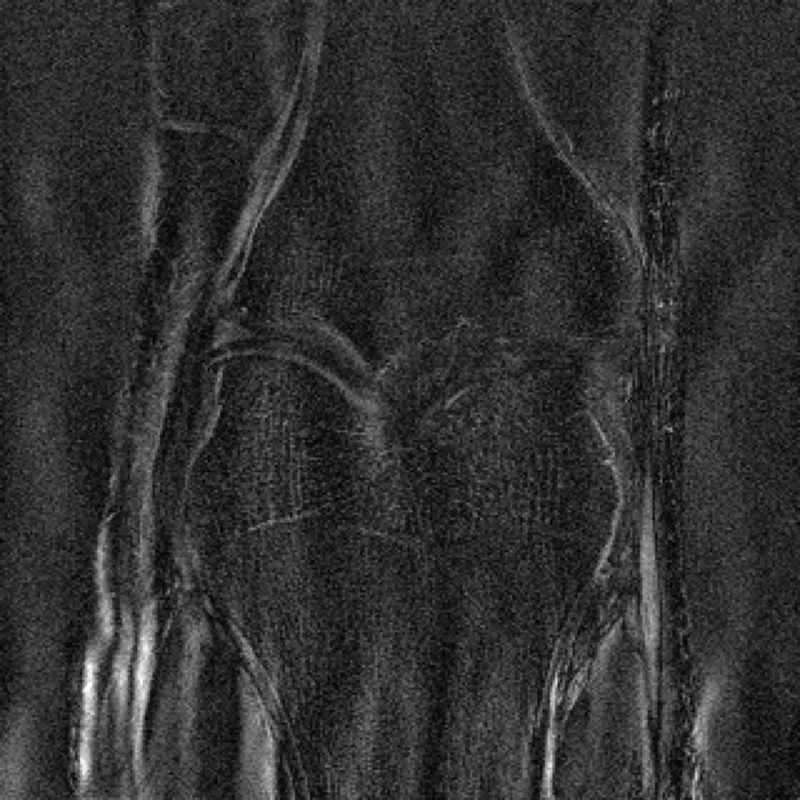

Suppose we are given a reconstruction network trained to solve (P0). The key idea we exploit is that the composition of with the original forward model , should act as an auto-encoder, i.e.,Β if we define the map by then by design we should have for any image sampled from the image distribution . See Figure 3 for an illustration in the case of undersampled MRI reconstruction.

The data used in the undersampled MRI experiments were obtained from the NYU fastMRI Initiative [45]. The primary goal of the fastMRI dataset is to test whether machine learning can aid in the reconstruction of medical images. We trained and tested on a subset of the single-coil knee dataset, which consist of simulated single-coil measurements. In all tests, we use complex-valued data, which interfaces with our deep networks by treating the real and imaginary parts of the images as separate channels. We measure reconstruction accuracy with respect to the center 320320 pixels of the complex IFFT of the fully-sampled k-space data. For the purpose of visualization, we display only the magnitude images in the following sections.